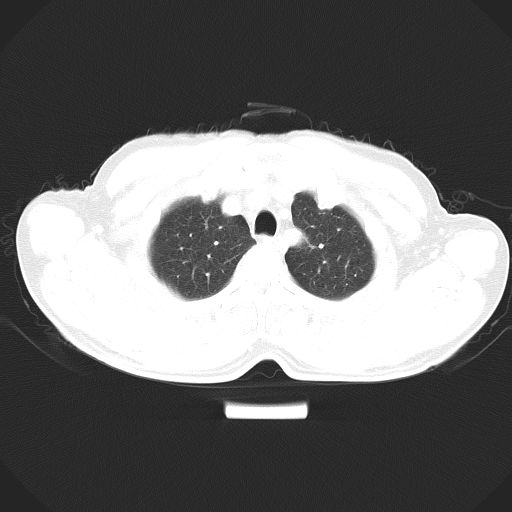

以下是引用心路寻觅在2010-3-1 10:23:00的发言:[br]1、考虑左肺上叶周围型肺癌[br]2、右上肺陈旧性病灶。[br][br][本贴已被 心路寻觅 于 2010-3-1 10:40:18 修改过]

以下是引用shuiyuan在2010-3-1 10:45:00的发言:[br]考虑左肺上叶中心型肺癌伴阻塞型炎症,邻近胸膜受侵。